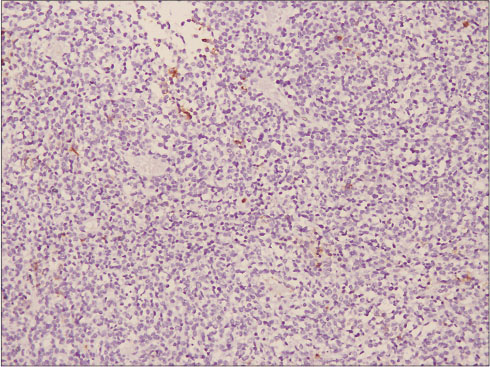

A 34-year-old female presented to us with increased bleeding per vaginum during her menstrual cycles associated with severe dysmenorrhea since 6 months. She was para 2, live 2, abortion 1. Her previous cycles were normal. She underwent endometrial biopsy outside 3 months back, and the histopathology reported as nonsecretory endometrium. She had failed medical management for AUB. On examination, her vitals were stable; general and systemic examination was within normal limits. Per abdomen examination revealed a soft abdomen with no mass or ascites. Speculum examination showed a healthy cervix and liquid-based cytology was reported as normal. On bimanual pelvic examination, uterus was anteverted, mobile, 12?14 weeks size. Ultrasound with Doppler flows revealed an anteverted bulky uterus of 10.2 cm ? 5.6 cm ? 4.1 cm with 14 mm ? 13 mm hypoechoic area suggestive of fibroid in the posterior wall of uterus not distorting the endometrial cavity. Endometrial thickness was 4 mm. Bilateral ovaries were normal. Doppler flows were within normal limits suggestive of benign lesion. The patient and her family were counseled and given various treatment options available for the management of her problem. They insisted on hysterectomy as a permanent treatment by laparoscopic approach. Patient was taken up for D/C followed by frozen section of endometrial curetting, total laparoscopic hysterectomy with bilateral salpingectomy with ovarian conservation. The frozen section revealed a benign endometrium. Intraoperative findings were a globular uterus, 14-week size with multiple seedling fibroids. On cut section of the specimen, cavity was regular. Myohyperplasia was present with multiple intramural small seedling fibroids with a single 2 cm ? 2 cm fibroid on the left posterior wall. Patient was discharged in a stable condition. Surprisingly, the histopathology report was suggestive of a single submucosal nodular lesion of 1.2 cm seen in the myometrium with infiltrative and focally permeative margins into myometrium [Figure 1]. Tumor showed discrete highly cellular high-grade round cell areas and hypocellular spindle cell component. The round cells had oval vesicular nuclei with irregular contours and focally prominent nucleoli with a moderate amount of eosinophilic cytoplasm. Hypocellular component showed fibromyxoid background with large bizarre cells with no increase in mitosis. Lymphovascular invasion was equivocal. On immunohistochemistry staining, the high-grade component was positive for Cyclin D1 and negative for CD10 [Figure 2] and [3]. Ki67 proliferation index was 15%?18%. The low-grade component was positive for CD10 and negative for Cyclin D1. Ki67 proliferation index was 1%?2%. HMB45 was negative for both the components.

|?Figure. 3? Immunohistochemistry: photomicrograph showing tumor cells to be negative for CD10 (IHC; ?100)